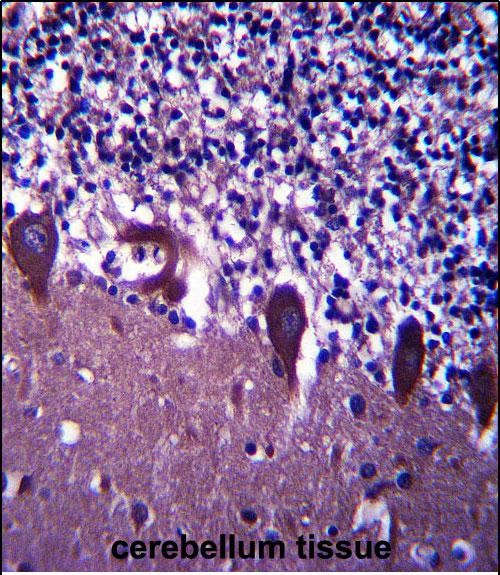

| IHC | 1/100-1/500 | Human,Mouse,Rat |